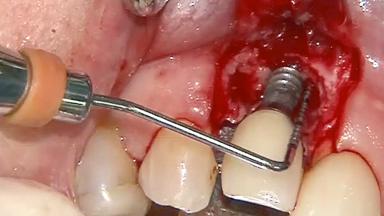

Surgical Management of Peri-Implantitis: Open-Flap Debridement with Seven-Year Follow-up After Treatment

This case describes both a surgical and an anti-infective approach for the management of peri-implantitis, including treatment of the entire dentition to eliminate any deep periodontal pockets that could serve as reservoirs for bacterial re-colonization at the implant site. A 65-year-old female patient was referred to the periodontist in 2013 for assessment and management of an infection at implant 12. On examination, probing depths at implant 12 were 11 mm with suppuration and bleeding on probing.